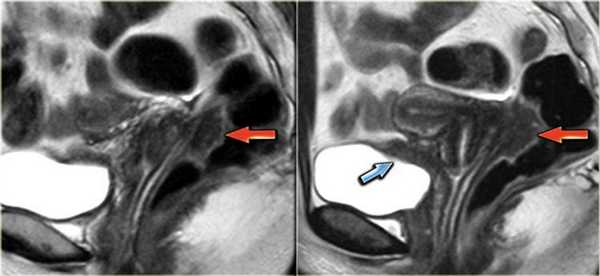

Покажет ли МРТ эндометриоз? На Т2 взвешенных сагиттальных МР-томограммах визуализируются два патологических веерообразных участка, дающих гипоинтенсивный сигнал (красные стрелки). Эти изменения типичны для эндометриоза с инфильтрацией стенки кишечника. Также определяется подслизистый отек, характеризующийся гиперинтенсивным сигналом со стороны отделов стенки кишки, расположенных ближе к просвету

Эндометриоз на МРТ малого таза. В случае циркулярного поражения эндометриоидная инфильтрация может приводить к сужению просвета кишечника. У пациенток при этом возможно изменение формы каловых масс (они становятся узкими в виде «карандаша») либо запоры. На Т2 взвешенных сагиттальных МР-томограммах определяется стеноз прямой кишки на ограниченном участке вследствие циркулярной инфильтрации